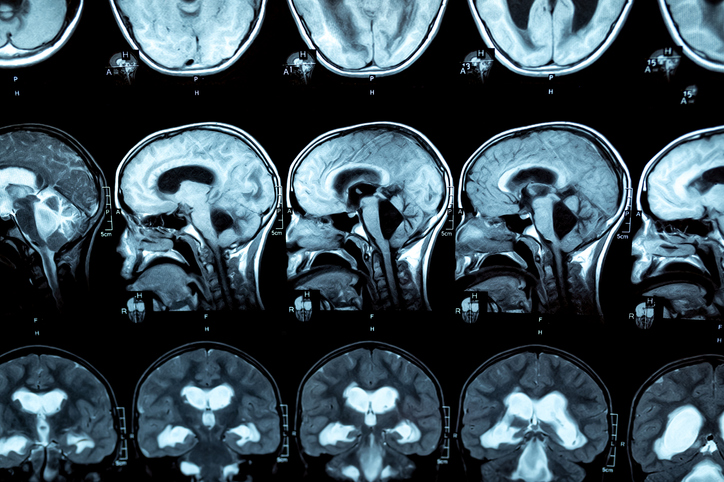

We offer many procedures and imaging tools to help your doctor get an accurate diagnosis. These include CT, MRI, and magnetic resonance venography, as well as lumbar puncture, intracranial pressure monitoring and nuclear medicine cystogram.